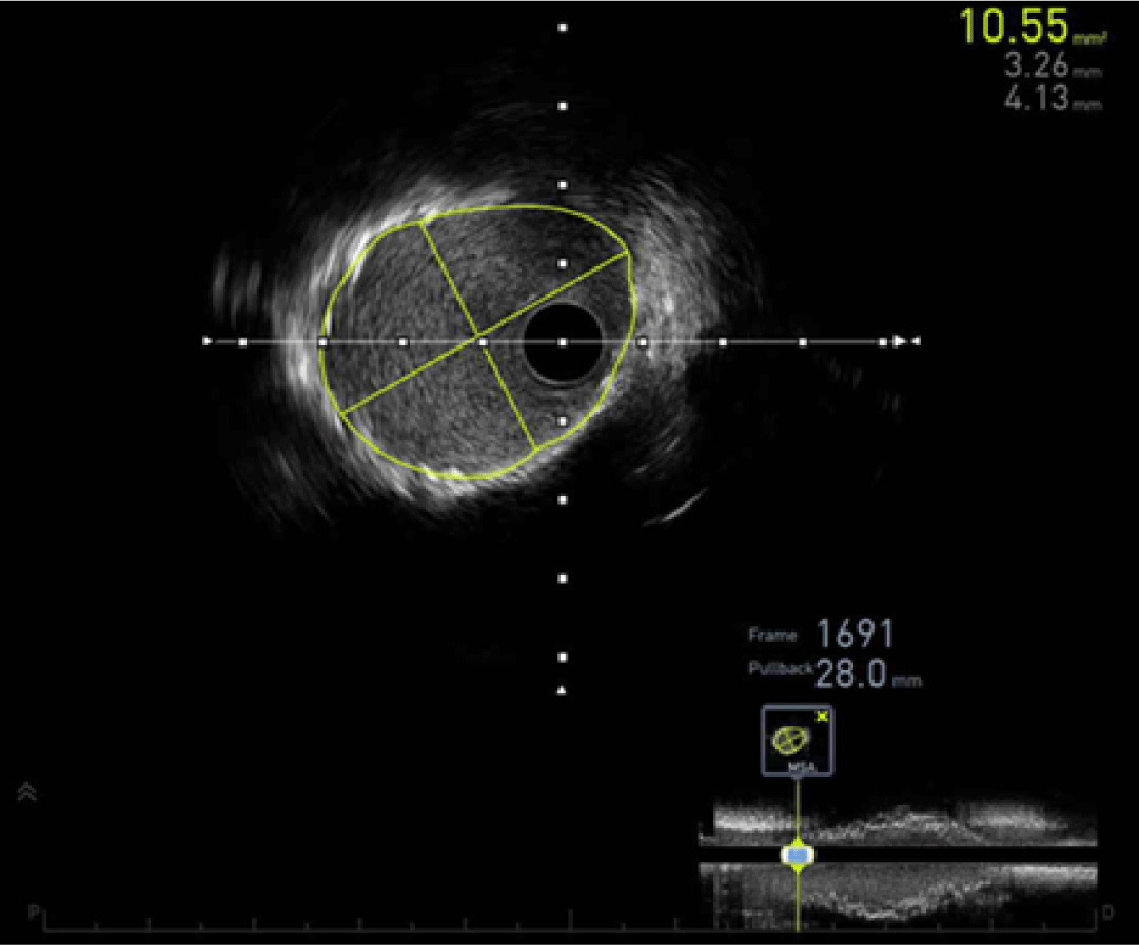

In patients with KD, the immediate procedural success rate of stent implantation has been reported to range from 86% to 100% in a limited number of cases [18,23,24,30–32]. Bare-metal stents, drug-eluting stents (DES), and covered stents have been used [18,23,24,30–32]. The large diameter of CAAs makes safe stent deployment challenging and increases the risk of stent migration in KD-associated coronary lesions [19,33]. Intravascular imaging, using either intravascular ultrasound (Fig. 3) or optical coherence tomography, is crucial for guiding treatment, as thrombus can obscure the true vessel diameter, potentially resulting in undersizing or improper stent placement [19]. Coronary stent implantation was widely regarded as a potential strategy to reduce restenosis and preserve coronary patency after balloon angioplasty [34]. However, a review of the literature revealed that late outcomes following coronary stent implantation were unsatisfactory, with adverse events occurring in 68% of cases, including complete occlusion, restenosis, stent migration, and new aneurysm formation [32]. Accordingly, the JCS guidelines advise against primary coronary stenting in this population [14].